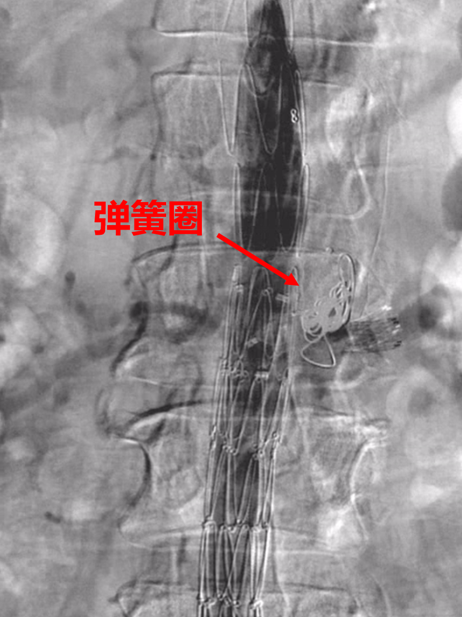

弓部小弯侧动脉瘤,外院TEVAR后IA型内漏

再干预方案:弹簧圈栓塞

弓上分支重建+

近端延伸支架

瘤腔内弹簧圈栓塞